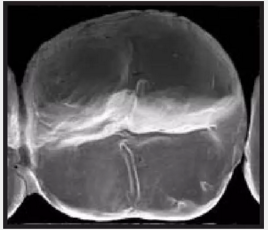

復(fù)合樹脂在即刻充填后,觀察其在電子顯微鏡下的掃描圖像,本次研究選擇了9種具有代表性的復(fù)合樹脂材料。

4.png

Filtek LS 3M ESPE